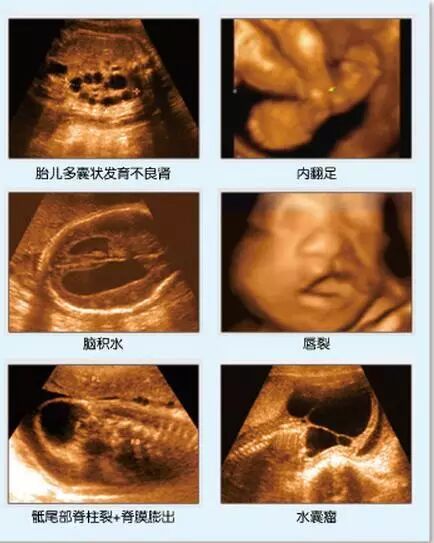

应用1:胎儿面部与唇腭裂的应用